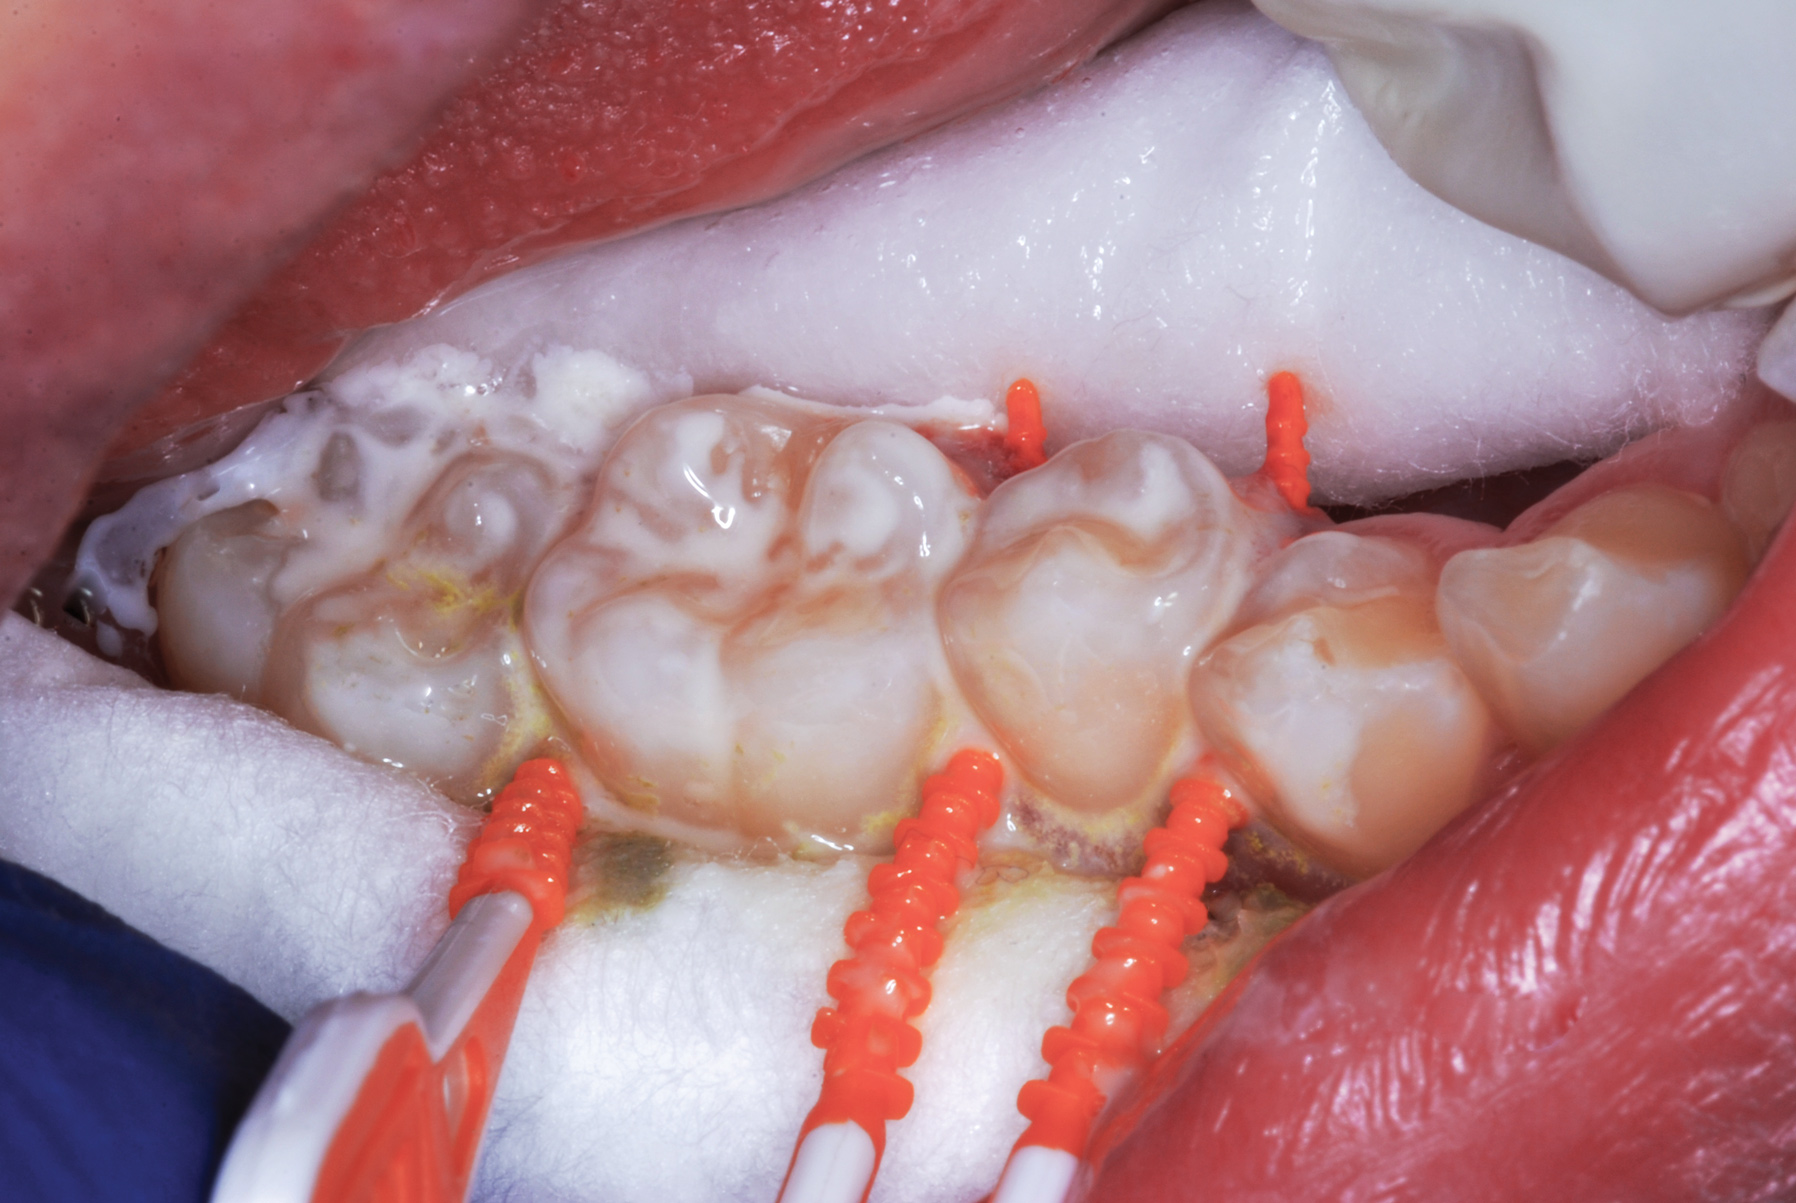

The authors' protocol for insertion of SDF-coated soft dental picks involves isolating the teeth with cotton rolls or other means, flossing the interproximal site to clear food debris and dental plaque, and then inserting a SDF-coated pick (Figure 1 and Figure 2) to saturate the contacting surfaces of the teeth with the fluid. This treatment is painless and requires no anesthetic. The pick should remain in place for at least 60 seconds and can be gently pulled in and out to agitate the fluid for enhanced surface coverage by capillary action. Additional SDF can be wiped on, using a small applicator, above the contact and in the buccal and lingual sluiceways. Excess fluid and any blood elicited may be blotted with a cotton swab. An additional 60-second insertion may be applied in the same way if there is radiographic evidence of a deeper decalcification or caries lesion. With the pick still in place, 5% (or 2.5%) fluoride varnish is painted over the treatment area, and the pick is then withdrawn.

Fig 4. Three thin soft dental picks were used simultaneously for SDF proximal surface saturations in a teenaged patient (Fig 3). After 60 seconds, the treated regions were covered with 5% fluoride varnish (Fig 4). A comparison can be seen of pre-SDF-treatment bitewing films (Fig 5) and 8-month post-SDF bitewing films (Fig 6) for the patient shown in Fig 3 and Fig 4. Radiolucencies were similar or improved, except for contact of maxillary first and second molars.

Figure 4